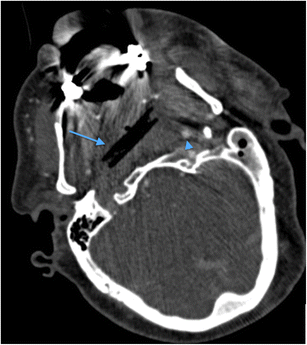

Axial MDCTA image through the infratemporal fossa of a 59-year-old man who fell on to a garden bamboo stick (thin blue arrow) which penetrated the left buccal region of the facial soft tissues, lodging and breaking-off in the retropharyngeal region of the nasopharynx and causing dissection occlusion of the right internal carotid artery (note the normal contralateral left internal carotid artery [blue arrowhead]). The geometric margin of the air-containing abnormality highlights the radiologic features consistent with an embedded foreign body fragment of organic material (wood). The patient subsequently developed a near-total thromboembolic right middle cerebral artery territory infarct (imaging not shown)